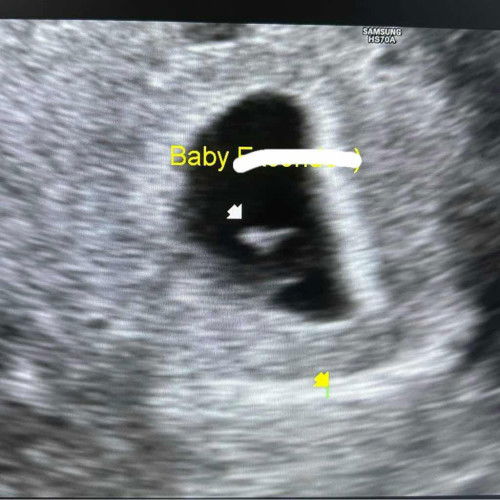

Irregular shaped gestational sac

Hi, I am already 6 week pregnant. I had may transvaginal yesterday and sabi ni Doc irregular daw ang shape ng gestational sac ko. 101bpm ang heartbeat ni baby. Any success stories po? Medyo worried ako na mamiscarriage.#sac #irregulargestationalsac